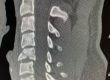

The goals of surgery include relieving the pressure on the spinal cord and nerve roots at all the affected levels and restoring the natural spinal alignment. The images show pre- and post-operative images of a 60-year-old female that had a successful 3 level anterior fusion procedure.